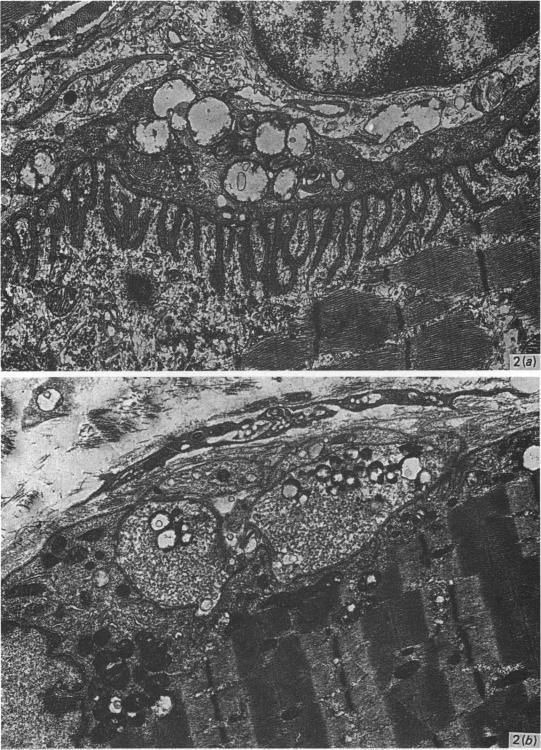

Electron micrographs of guinea-pig oesophageal striated muscle have been subjected to quantitative assessment. The results show that whereas the motor end-plates are considerably simpler than those of control hindlimb muscles, the Z-line width and M-line bridges are those of fast-twitch, oxidative and glycolytic fibres. Guinea-pig oesophageal striated muscle continues to defy classification into the normally accepted subtypes for skeletal muscle and should thus be considered as an example of 'visceral striated muscle'.

摘要

豚鼠食管横纹肌的电子显微镜照片已接受定量评估。结果表明,虽然运动终板比对照后肢肌肉的运动终板要简单得多,但Z线宽度和M线桥却是快肌纤维、氧化型纤维和糖酵解型纤维的特征。豚鼠食管横纹肌仍然难以被归类为骨骼肌通常公认的亚型,因此应被视为“内脏横纹肌”的一个例子。